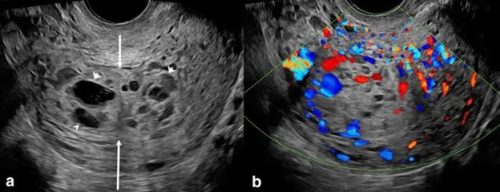

Thai trứng là gì? Thai trứng, hay còn gọi là chửa trứng, là một tình...